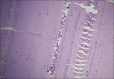

Histopathological examination is considered as gold standard procedure for arriving at a final diagnosis of various lesions of the human body. However, it is limited by a number of alterations of normal morphologic and cytological features that occur as a result of presence of artifacts. These artifacts may occur during surgical removal, fixation, tissue processing, embedding and microtomy and staining and mounting procedures. They can even lead to complete uselessness of the tissue. It is therefore essential to identify the commonly occurring artifacts during histopathological interpretations of tissue sections. This article reviews the common artifacts encountered during slide examination alongside the remedial measures which can be undertaken to differentiate between an artifact and tissue constituent.